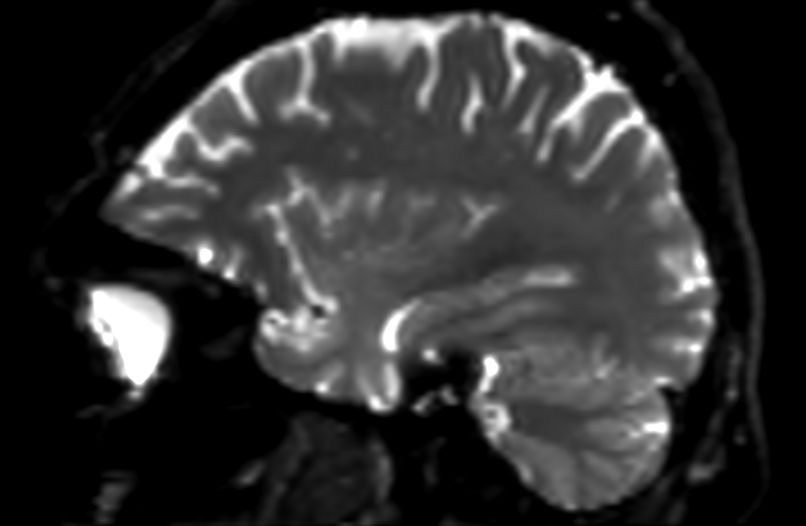

Sagittal 3D VIEW - T2w FLAIR

Sagittal 3D VIEW - T2w TSE